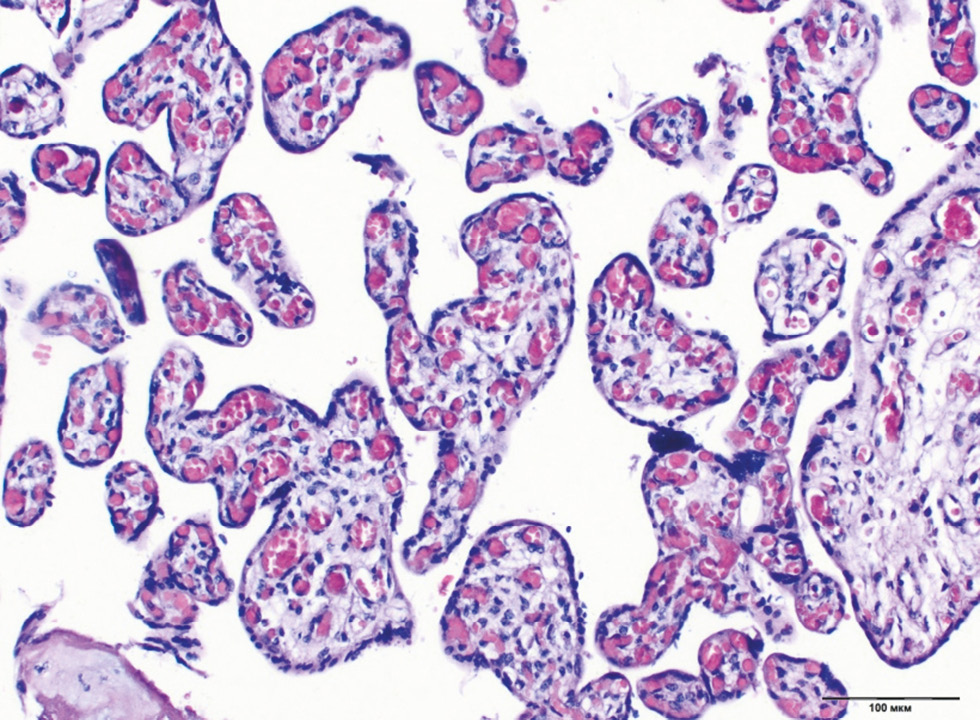

Chronic placental insufficiency was typical for all groups of DM and PE, in contrast to the control group (p < 0.0001). Placental insufficiency was registered in 39.6% of cases in Group 4 (type 2 DM on a diet), 37.2% in the type 1 DM group with MII, whereas pathological immaturity of villi was noted more often in the same groups (14.2% and 19.5%, respectively). In general, pathological immaturity of villi was typical for all groups of DM (9.5%–19.5%, p < 0.0001). The predominance of intermediate immature villi was a characteristic of type 1 DM with MII (13.3%, p = 0.036) (Fig. 1). The dissociated form of chronic placental insufficiency was most often detected in DM (16.3%–26.1%) (Fig. 2). The prevalence of sclerosed villi (0.4%–3.3%) and premature maturation of villi (0.4%–5.0%) were revealed less frequently. In the PE group, the premature maturation of villi was noted often (7.7%, p < 0.0001). In the control group, 93% of placentas corresponded to gestational age (Table 2).

Fig. 1. Chronic placental insufficiency with a predominance of intermediate immature chorionic villi with hypervascularization and congestive plethora in type 1 DM. Staining with hematoxylin and eosin, ×100